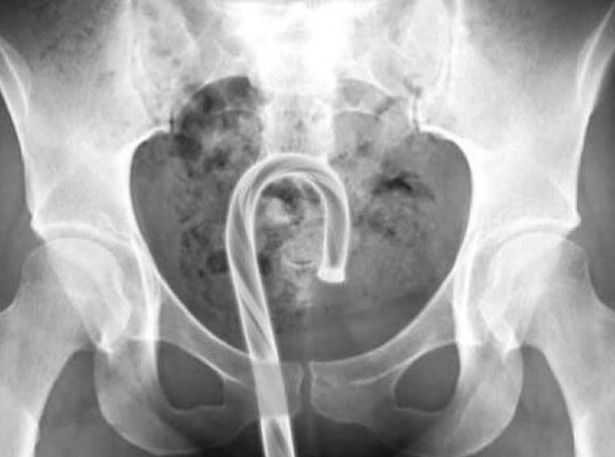

Đặc biệt, có trường hợp một cô gái trẻ sử dụng kẹo que hình gậy trang trí Giáng sinh để thử cảm giác mới. Kết quả, chiếc kẹo dính, kẹt luôn trong cơ thể. Ảnh chụp X-quang cho thấy rõ ràng một cây kẹo và một vật trang trí cây thông Noel nằm trong trực tràng của bệnh nhân.